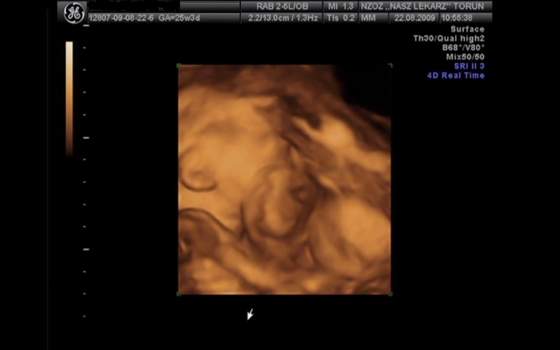

Ja tak mialam w pierwszej ciazy i tego terminu sie trzymalismy(z pierwszego udg) i wyszedla najbradziej trafnie. Wiadomo, pozniej dzidzia rosnie "skokami" i rozne terminy wychodza. Ja mialam na 28.08, urodzilam 29.08(...)Lekarz zapytał mnie o datę ostatniej miesiączki. To ważne, bo ja nie mam liczonej ciąży od daty ost miesiaczki, tylko od pomiaru synka na USG 2d. No i na 4d się nie zdziwił, że to 26 tc.